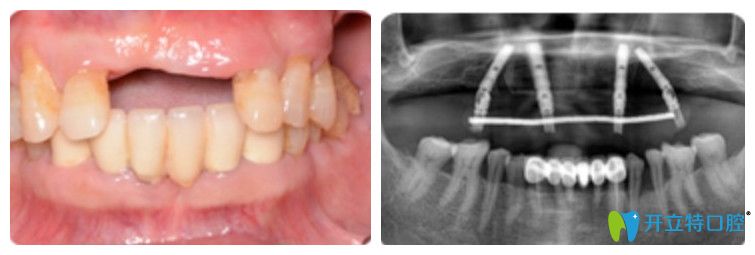

王先生在優(yōu)貝口腔做完種植牙前后圖

王迪院長(zhǎng)說即刻用種植牙并不是單純的種植技術(shù),還要從術(shù)前的全景數(shù)字化口腔檢查、口腔環(huán)境預(yù)評(píng)、牙槽骨條件測(cè)量等檢查形成專屬種植方案。通過各項(xiàng)檢查發(fā)現(xiàn):王叔佩戴假牙時(shí)間比較長(zhǎng),導(dǎo)致牙槽骨有點(diǎn)萎縮,剩下的那幾顆牙齒牙根也已經(jīng)松掉了,沒有保留的價(jià)值,需要先拔掉,然后做ALL—on—4即刻種植牙。

王迪院長(zhǎng)利用4顆種植體,兩顆種植體垂直植入牙槽骨內(nèi),另外兩顆采取傾斜角度植入牙槽骨內(nèi),然后在種植體的基臺(tái)安裝“拱形連橋”牙冠,實(shí)現(xiàn)半口牙種植。

王先生半口牙種植前后的變化